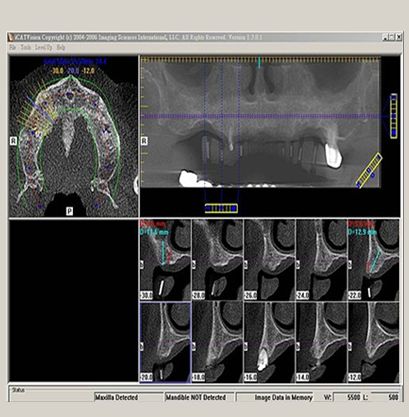

3D口腔電腦斷層拍攝

植牙時提供,非診所本身具備

3D口腔電腦斷層掃描,其輻射劑量比傳統斷層掃描減低非常多,可提供3D影像 ( 避免影像重疊 )、1比1真實清析骨頭影像 ( 可清楚觀察神經管、鼻竇位置 ) 、頰側、舌側 ( buccal-lingual ) 真實寛度、骨頭密度數據。 這項設備價位也極高但只在植牙等特定狀況才需拍攝,且一般一人只拍攝一次,因此我們選擇搭配具備放射師的專業影像中心,在患者需要時才去拍攝,當確定植牙時由診所支出此拍攝費用。